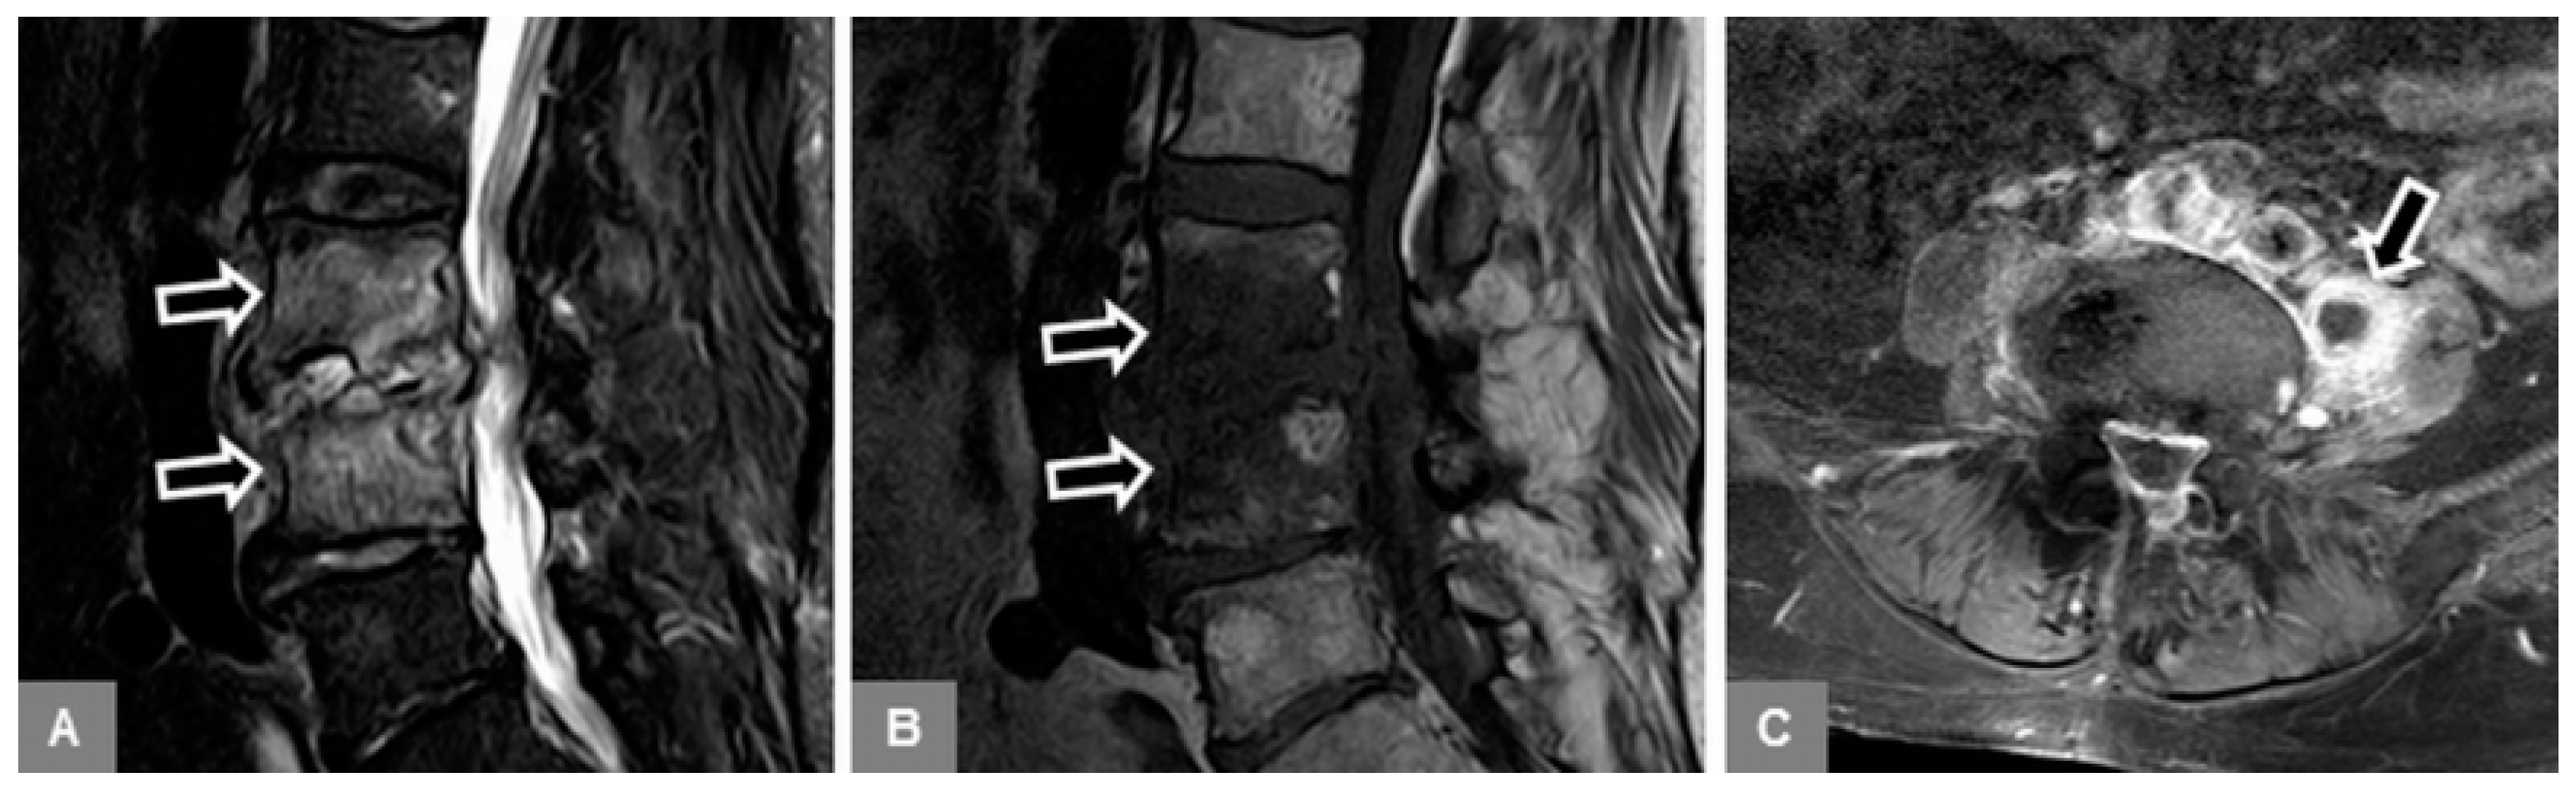

3.1. Bone Marrow Edema Extent, T1-w Signal Ratios of Edema to Unaffected Bone, and Visual T1-w Signal Assessment

3.2. Vertebral Endplate Contour